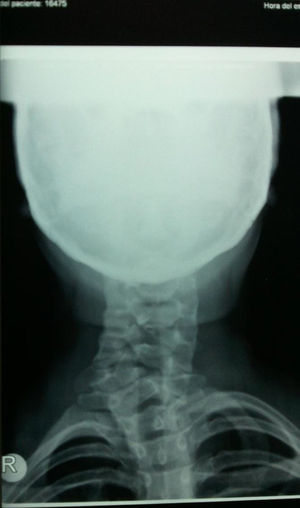

Ante el antecedente del traumatismo se solicita una radiografía de columna cervical en 2 proyecciones anteroposterior y lateral, donde se observa rectificación cervical e imágenes no definidas a nivel del cuerpo de los últimos arcos vertebrales, por lo que se solicita una tomografía axial computarizada (TAC) cervical.

La TAC cervical informa de la existencia de defectos de fusión de los arcos anterior y posterior del atlas con presencia de bordes escleróticos en el arco anterior. Se aprecia la existencia de una hemivértebra derecha C7 (cervical 7) que condiciona escoliosis de la columna cervical. Rectificación de la columna cervical. No se observan líneas de fractura agudas, ni afectación del canal medular.

En el caso que presentamos, si no se hubiera valorado la radiografía anteroposterior habría pasado desapercibida la malformación a nivel del cuerpo vertebral de la C7, así como en la radiografía lateral el defecto de fusión a nivel del atlas; por tanto es necesaria una sistemática en la valoración de las radiografías de columna cervical aunque la clínica no sea muy llamativa (figs. 1 y 2).